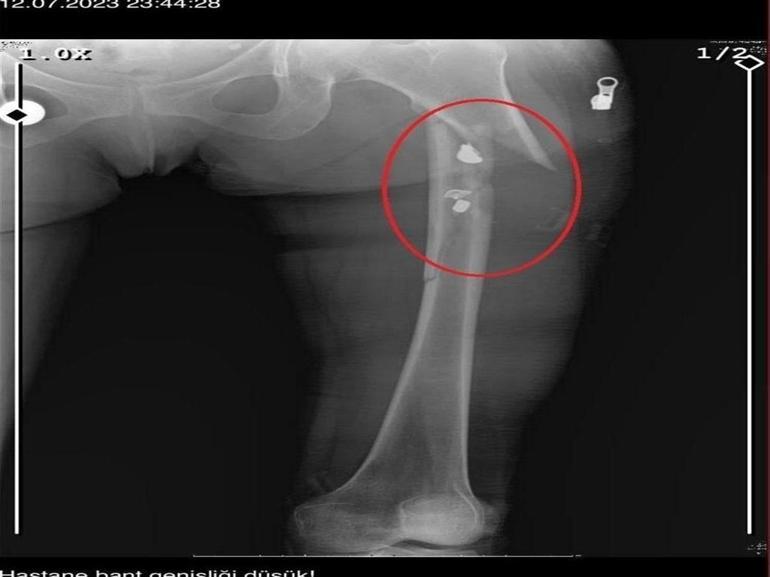

İlyas Sarıkaya, sevgilisi Fatma O.'yu da 8 kurşunla vurup, yaraladı. Arkadaşı Özaslan'ın cesedini önce çarşafa sonra da streç filme sarıp bantlayan Sarıkaya, eczaneden aldığı sargı bezi ve ilaçlarla pansumanını yaptığı sevgilisine yaralı haldeyken 21 gün boyunca cinsel saldırıda bulundu.

Fatma O., annesine yazdığı mesajda, “Odada ceset var. Telefon dinleniyor. Bana 8 el ateş etti. Yaralıyım. Polisi görürse önce beni öldürecek. Onu parayla kandırıp, evden çıkartın. Sonra da beni alın” dedi. Fatma O.’nun annesi, bu mesaj sonrası polise gidip şikayette bulundu. Polis, Fatma O.'nun annesi aracılığıyla Sarıkaya ile iletişime geçti. Fatma O.'nun annesi, telefonla aradığı Sarıkaya'yı, kızına para götürmesi için evine çağırdı. Ekipler, parayı almaya gelen Sarıkaya'yı kendilerine silah çekmesine rağmen yakaladı. Eve giden ekipler, ağır yaralı haldeki Fatma O. ve kokmaya başlayan cesetle karşılaştı. Emniyetteki işlemlerin ardından Sarıkaya tutuklanıp, hakkında dava açıldı.